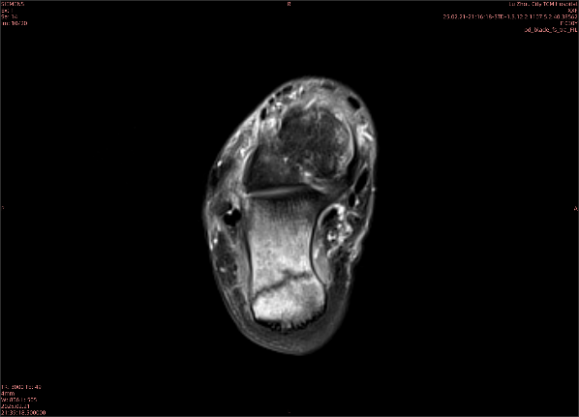

舉例圖像

圖1

專業(yè)解釋看不懂沒關(guān)系,大家看圖1和圖2就可以了,這是同一個患者跟骨的磁共振和CT圖像,圖1的紅色箭頭指示的黑線就是磁共振圖像顯示的骨折線,一目了然。而對比圖2的CT圖像上并未顯示異常。